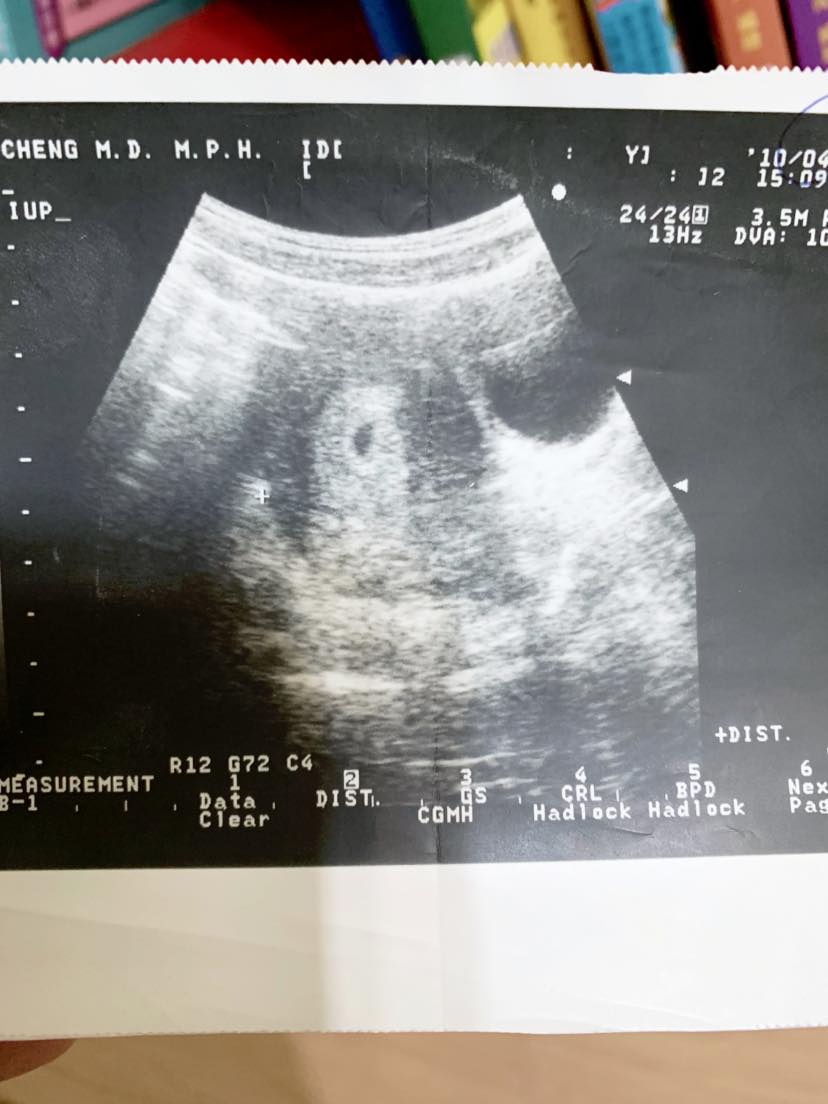

我就這麼哭著走進一個老醫生的診間,哭著躺上診療床,邊哭邊緊盯著老醫生的一舉一動,看著他用舊式的設備在我的肚皮上搜索探勘胎胚的心跳,整個診療時間已超過原本產檢診所的3倍之長。[蹦蹦、蹦蹦、蹦蹦、蹦蹦] ~ 突然聽見好像火車一節一節進入隧道聲音⋯天!#是心跳聲!當下我跟陳崇儒立馬爆哭,不同於走進診間時的悲傷,是感動非常的眼淚。醫生:「哎呀~真調皮!怎麼躲在這呢?很不容易照到欸。」我看著超音波畫面的小點點,喊了一句「小芝麻!#就叫你小芝麻。」